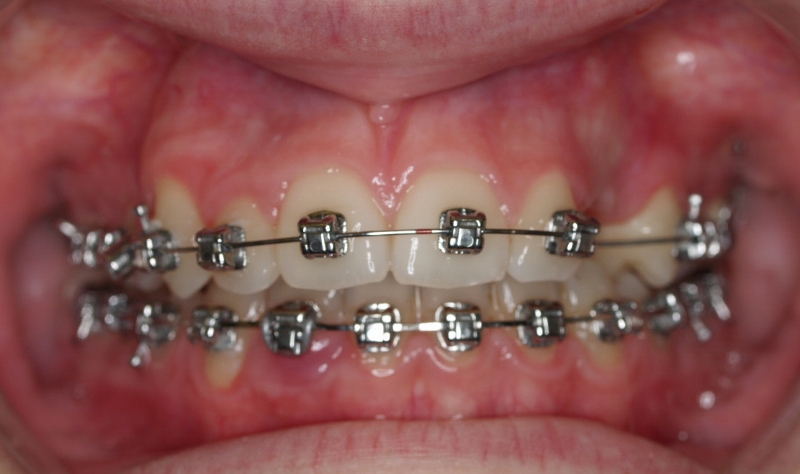

Clase II paciente 15 años

La paciente O.O. acude a nuestra consulta por:

– Canino 13 e incisivo lateral 42 en posición ectópica.

– Canino 23 incluido.

Con lo que decide realizarse un tratamiento de ortodoncia de duración de 24 meses con brackets damon Q.

CASO COMPLETO: